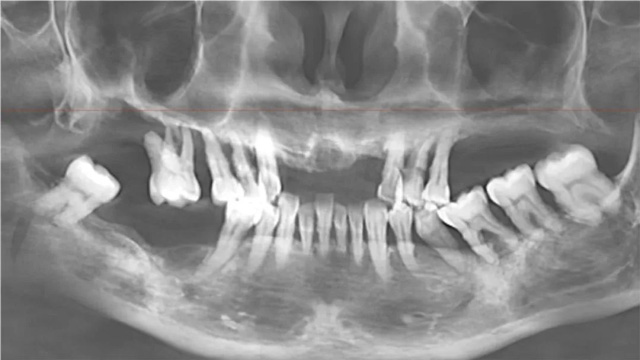

周先生半口种植前后全景片

安女士半口种植全景片(种植前)

安女士半口种植全景片(种植后)